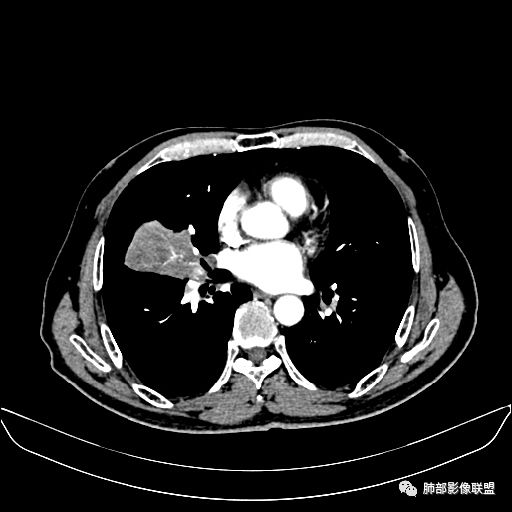

动脉期

老年男性,因“咳嗽咳痰1月余。”入院。病程中咳嗽咳痰,咳黄白痰,间断咯少许鲜红色痰血。PPD阳性。胸CT:右肺中叶外侧段支气管管腔阻塞,大片实性病变,病灶边缘光滑,部分边缘膨隆,可见分叶,肺门及纵隔可见肿大淋巴结,并可见钙化。增强可见病灶明显强化,而且延迟强化明显,病灶内多发低密度区,内见血管影,血管变细、部分血管破坏。考虑恶性病变可能性大,鉴别慢性肉芽肿性病变。

胸CT:跨叶大肿块,主体在中叶,右中叶外侧段支气管阻塞,病灶部分边缘膨隆,可见分叶,部分边缘平直,肺门及纵隔可见肿大淋巴结。增强病灶不均匀强化,延迟强化明显,病灶内多发低密度区,内见血管飘浮,部分血管变细、模糊。考虑:恶性病变可能性大,大细胞?淋巴瘤?鉴别慢性肉芽肿性病变。

右肺中叶软组织肿块,外围向内生长,叶间胸膜向前内移位,肿块近肺门侧跨叶,中叶外侧段支气管截断,密度不均匀,双侧肺门及隆突下见肿大淋巴结,增强后呈中度不均质强化,肺动脉供血,多发坏死区,边界尚清,坏死区域内见结构,结合病史考虑恶性,鉴别诊断1结核,爬行征是沿支气管树分布,外宽,内窄,周围有卫星灶,内气管狭窄后扩张,此例沿叶间胸膜长轴分布,气管有截断,不典型。2炎性肉芽肿,符合的地方下方层面增强后延迟性轻度环形强化,不符临床无发热等急性感染病史,实验室指标不符,病灶周围渗出及慢性炎性改变有,不明显。

墨西哥仙人掌征---结核        影像上结核灶,粗大的均匀枝干,推测是支气管囊状扩张引起的,在非支气管区,形成圆形坏死囊群;如果这些坏死比较稀薄,又遇到扩张支气管,就会形成粗大的“墨西哥仙人掌”。结核引起的支气管近端炎症纤维化,可以造成支气管阻塞,从而将干酪样坏死物封堵在管腔内。仙人掌主干内部应该是干酪为主,稀薄的,具有流动性,时间久了会出现钙化。

结核坏死与鳞癌鉴别有一点是结核坏死没有方向性,鳞癌有。鳞癌靠近支气管近端部分,血供容易维持,不易坏死,所以坏死靠外侧。而结核干酪样坏死,把一定体积的流动性坏死物,包裹起来,什么形状最省料?坏死物包裹,表面积最省的自然是圆球形,而遇到支气管,坏死物一多,就把支气管撑大了。包裹物是就地取材,扩张的支气管就成了包裹结构。